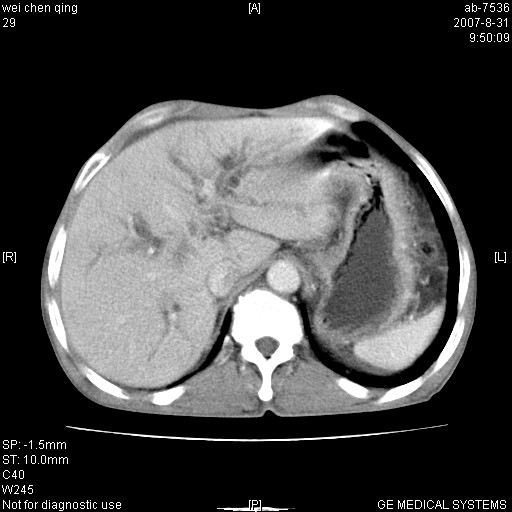

以下是引用zyyzzy在2007-8-31 14:34:00的发言:[br]该病人肝内胆管扩张,胆囊及胆总管未见明显扩张。在倒数第9层图像上可看到左右肝管结合部(肝总管)有软组织影,此处应薄层扫描。考虑肝总管占位(ca)、腹水。[br]